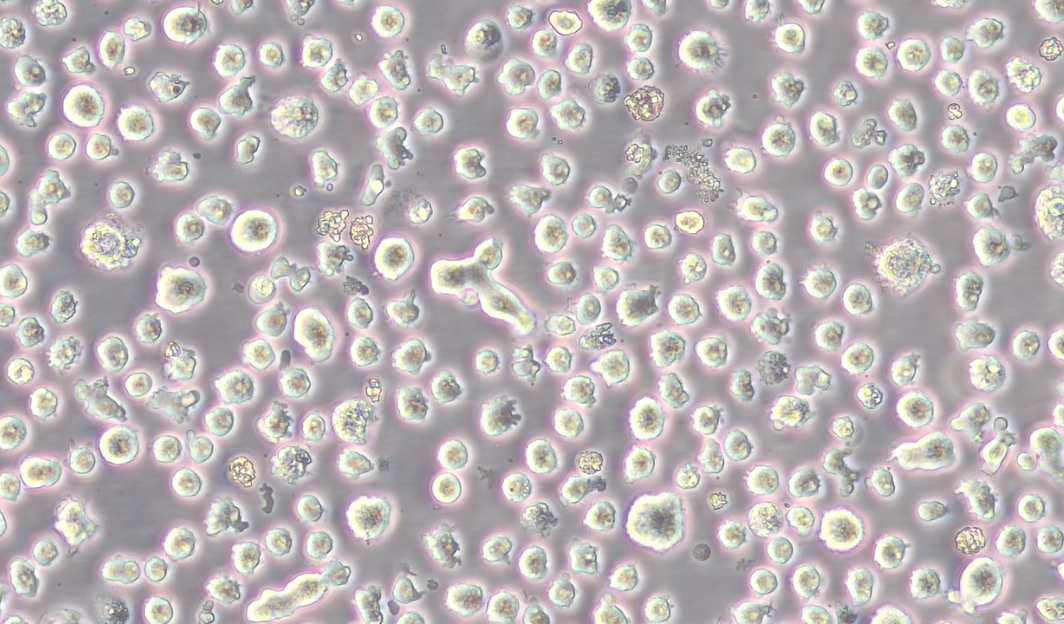

形態 |

淋巴母細胞樣 |

生長特征 |

懸浮生長 |